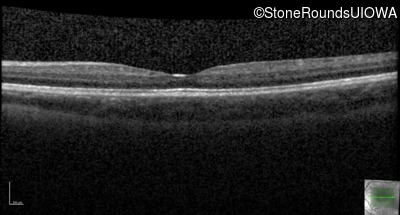

This 6 year old boy first experienced difficulty reading and seeing the blackboard at age 5.

| Age at visit: 14 years |

| Age at visit: 14 years (Visit 2) |